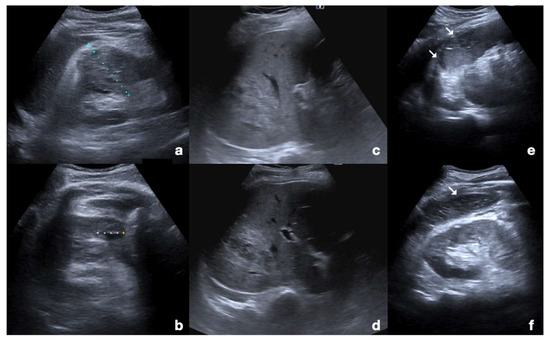

Examination starts with the non-enhanced US. All parenchymatous organs and the peritoneal cavity are investigated to determine the presence of parenchymatous injuries that would need to be deeply studied following injection of the UCA. As there is limited time to scan each organ following the injection due to the timing of each vascular phase, it is important to find areas requiring further investigation before the injection is administered (Figure 1) [30].

Figure 1.

Non-enhanced US of parenchymal injuries. (a) Longitudinal view of the right kidney adequate to appreciate the renal parenchymal hematoma in its whole extension; (b) axial view of the same kidney showing another smaller hematoma. (c,d) Axial views of the liver showing a wide lacero-contusive area in the right lobe (arrows). (e,f) Multiple lacero-contusive areas of the spleen (arrows).